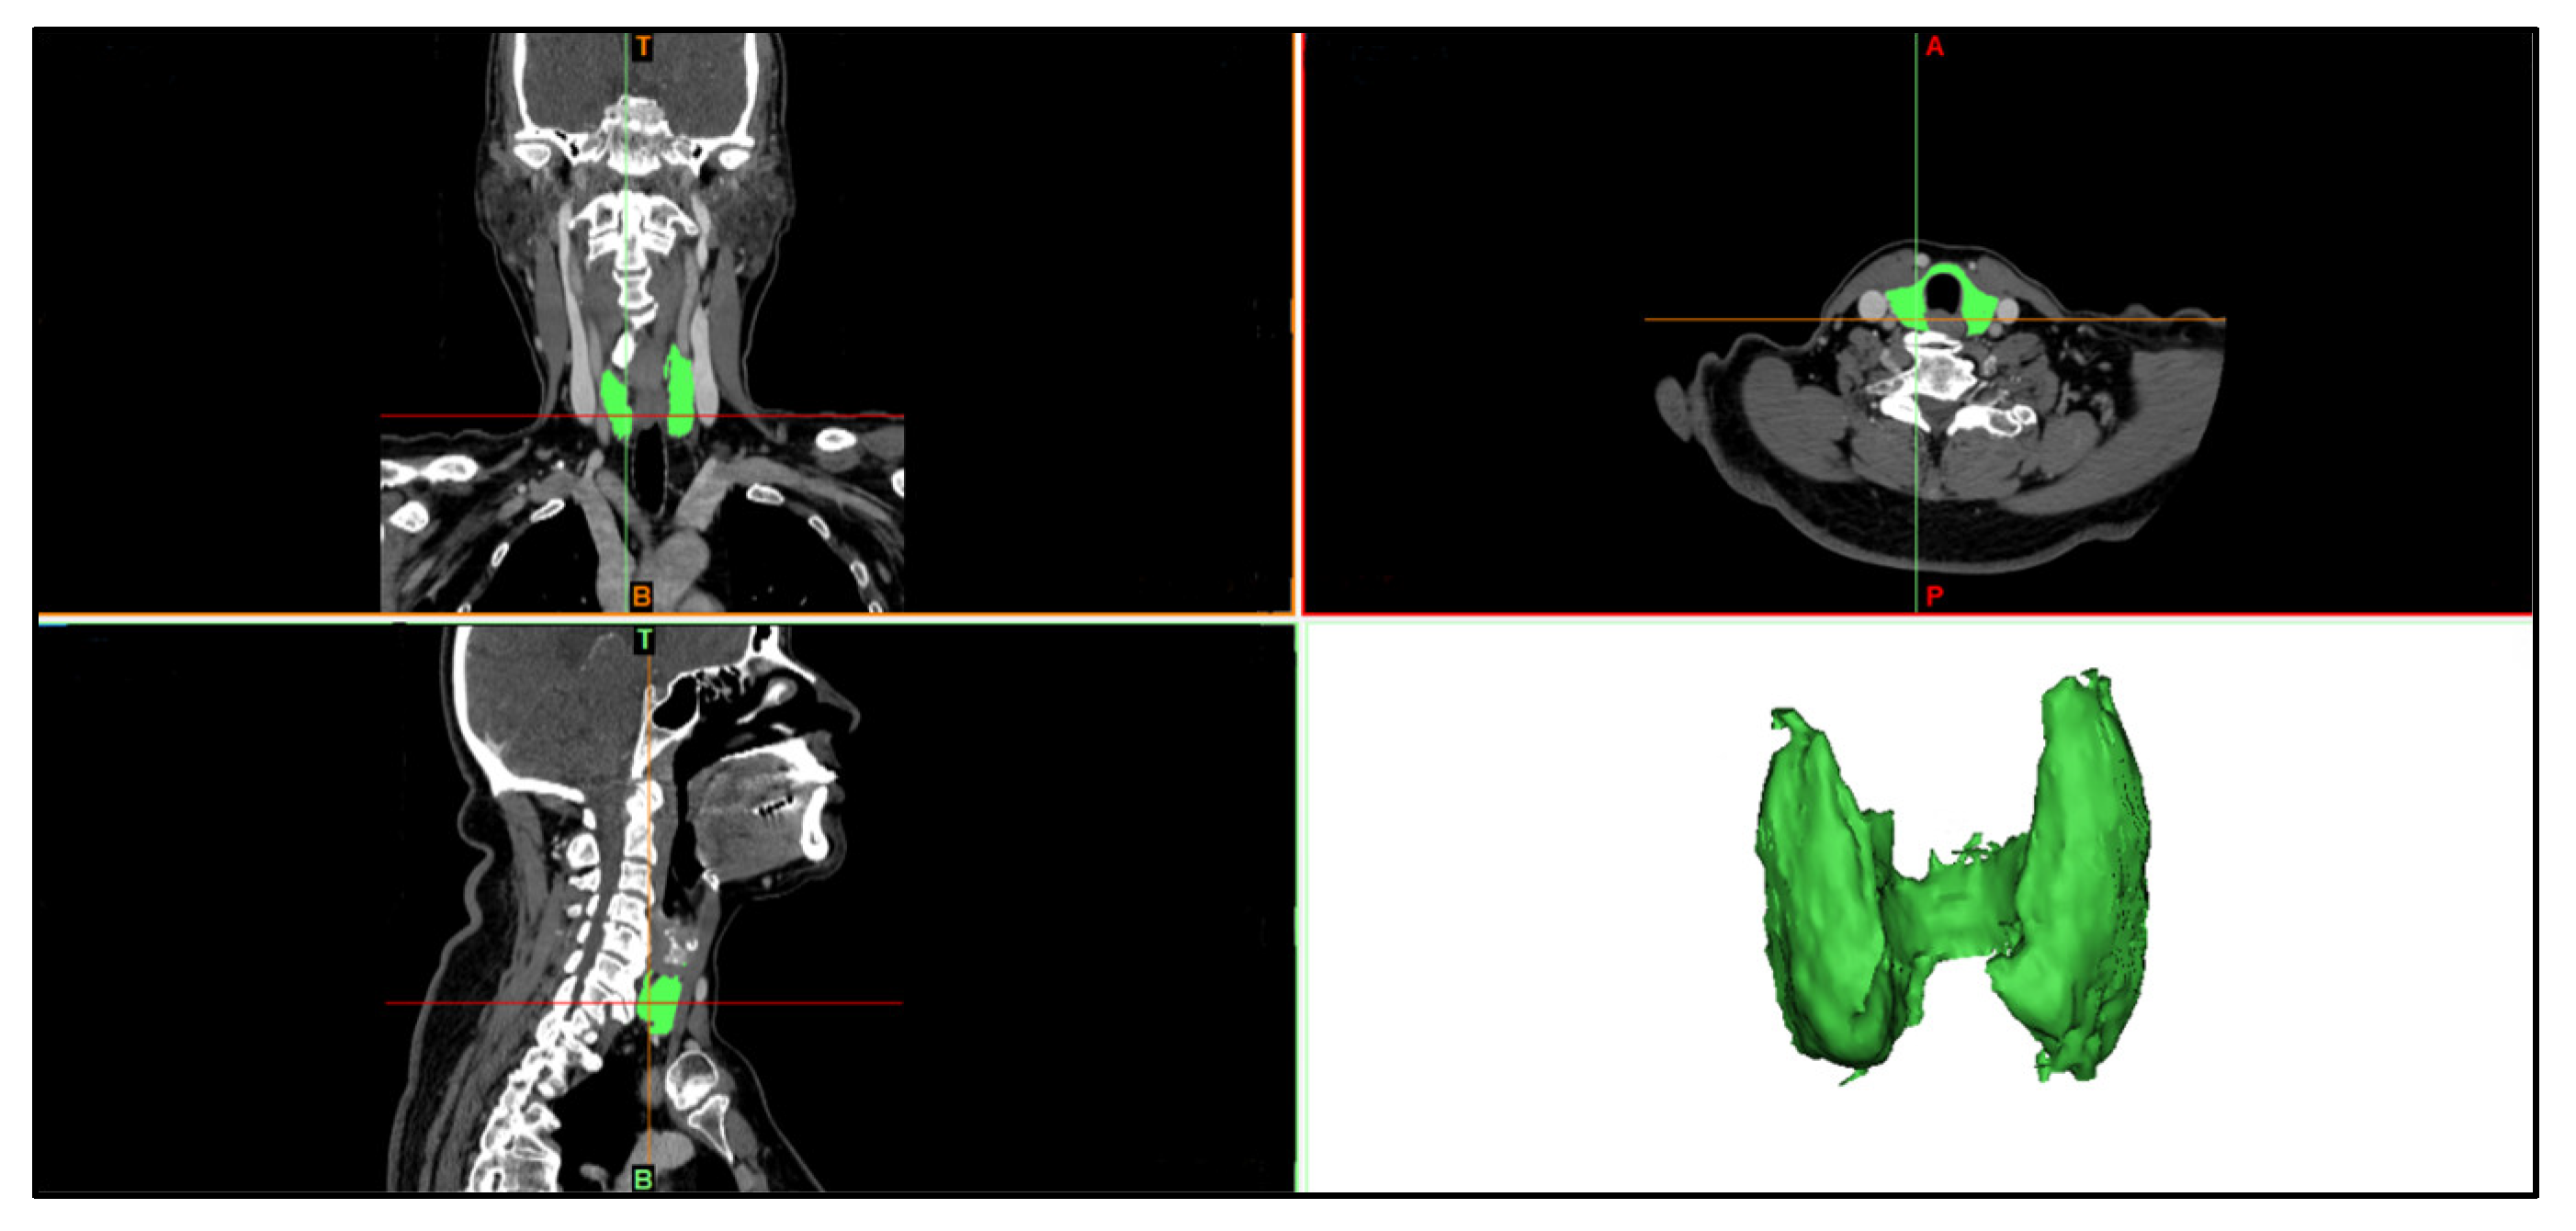

3.2.1. Segmentation of the Neck Region and Inner Structures

4.1. Segmentation Results